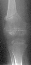

This patient is an 11 year old white male with a diagnosis of Multiple Epiphyseal Dysplasia (MED). Initially he presented with x-rays revealing mild genu valgum which progressed such that he required surgery. He had supracodylar osteotomy which was performed in 1993 for genu valgum . He was last seen in August 1995 for low back pain for which he was prescribed stretching exercises. Since the last visit he has had no problems with his back and denies any complaints in his lower extremities, with the knee valgus remaining stable .

Examination revealed a significantly obese boy in no acute distress. Examination of his back showed no evidence of any curvature. There was no tenderness of his entire spine. Examination of his legs revealed bilateral genu valgum with an intermalleolar distance of 13.5 cm. There was no evidence of any knee effusion or tenderness of the knees. Neurovascular status of the lower extremities was normal with 5/5 muscle tone bilaterally.

In radiograms, the principal findings are the delay and irregularity of ossification of the epiphyses, which are markedly fragmented and mottled. They appear flattened.